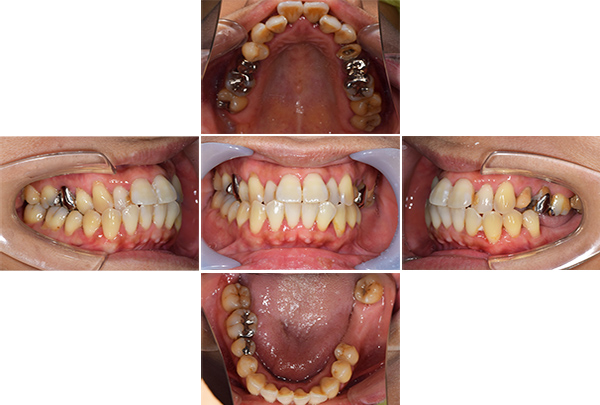

口腔内写真

【担当医師所見】

咬合平面の整頓の必要性 有

交叉咬合、オーバージェットの是正

前歯舌側の歯石

歯周病の治療の必要性

ブラッシング方法の教授

矯正中

左右上下合わせて4本の抜歯を行った

①前歯もキレイに並んできました

②上の歯が外側になり、交叉咬合がなくなりました

③左上の出ていた歯を元の位置までもどしています